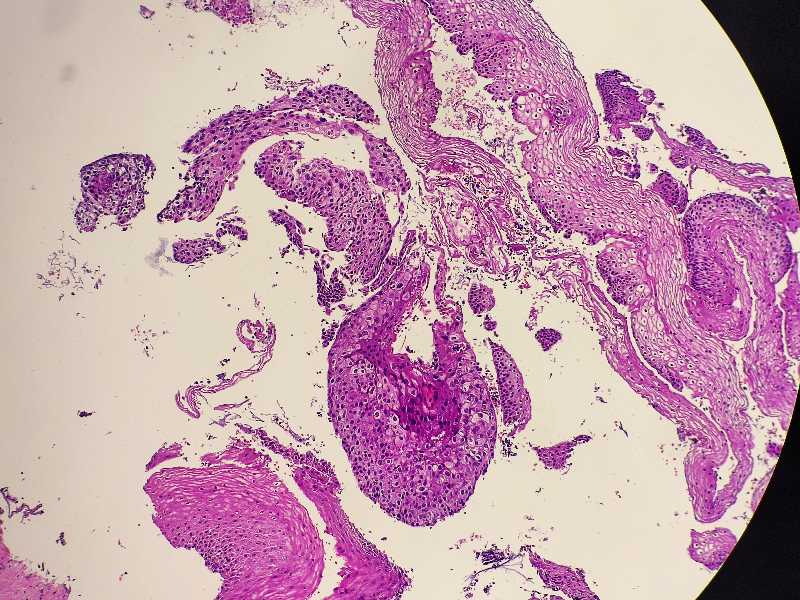

女59岁宫颈活检HPV58+